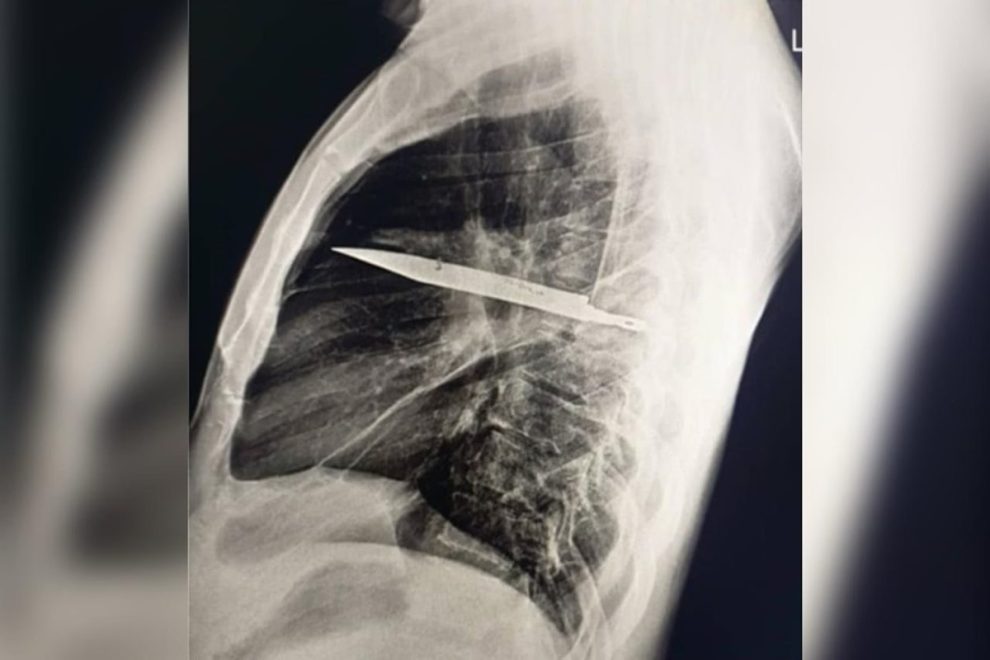

Um homem de 44 anos descobriu que viveu por oito anos com uma faca alojada no peito sem saber. A revelação veio depois que ele procurou atendimento médico na Tanzânia por causa de secreção com mau cheiro logo abaixo do mamilo direito.

No caso, publicado no Journal of Surgical Case Reports em 31 de maio, o paciente relatou que não sentia dor no peito, dificuldade para respirar, tosse ou febre, e apresentava sinais vitais normais, o que deixou os médicos intrigados.

Enquanto os profissionais investigavam o caso, o paciente lembrou que, quase 10 anos antes, havia se machucado durante uma briga, sofrendo cortes no rosto, nas costas, no tórax e no abdômen. Na época, recebeu suturas, mas não passou por exames de imagem, já que não havia suspeita de que algum objeto tivesse permanecido no corpo.